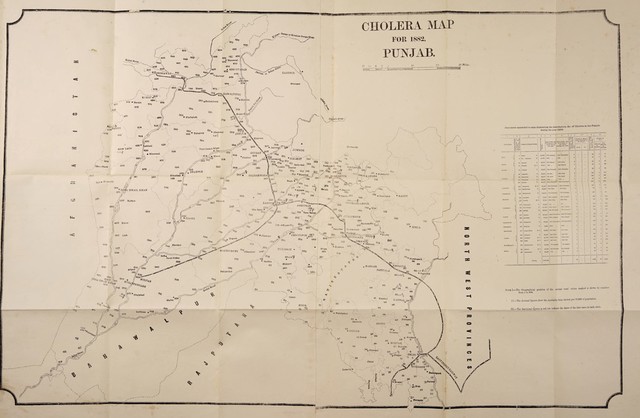

Report on the sanitary administration of the Punjab and proceedings of the Sanitary Board for the year ... and the report on sanitary works for.

- Punjab (India). Sanitary Board.

- [1882]

Credit: Report on the sanitary administration of the Punjab and proceedings of the Sanitary Board for the year ... and the report on sanitary works for. Source: Wellcome Collection.